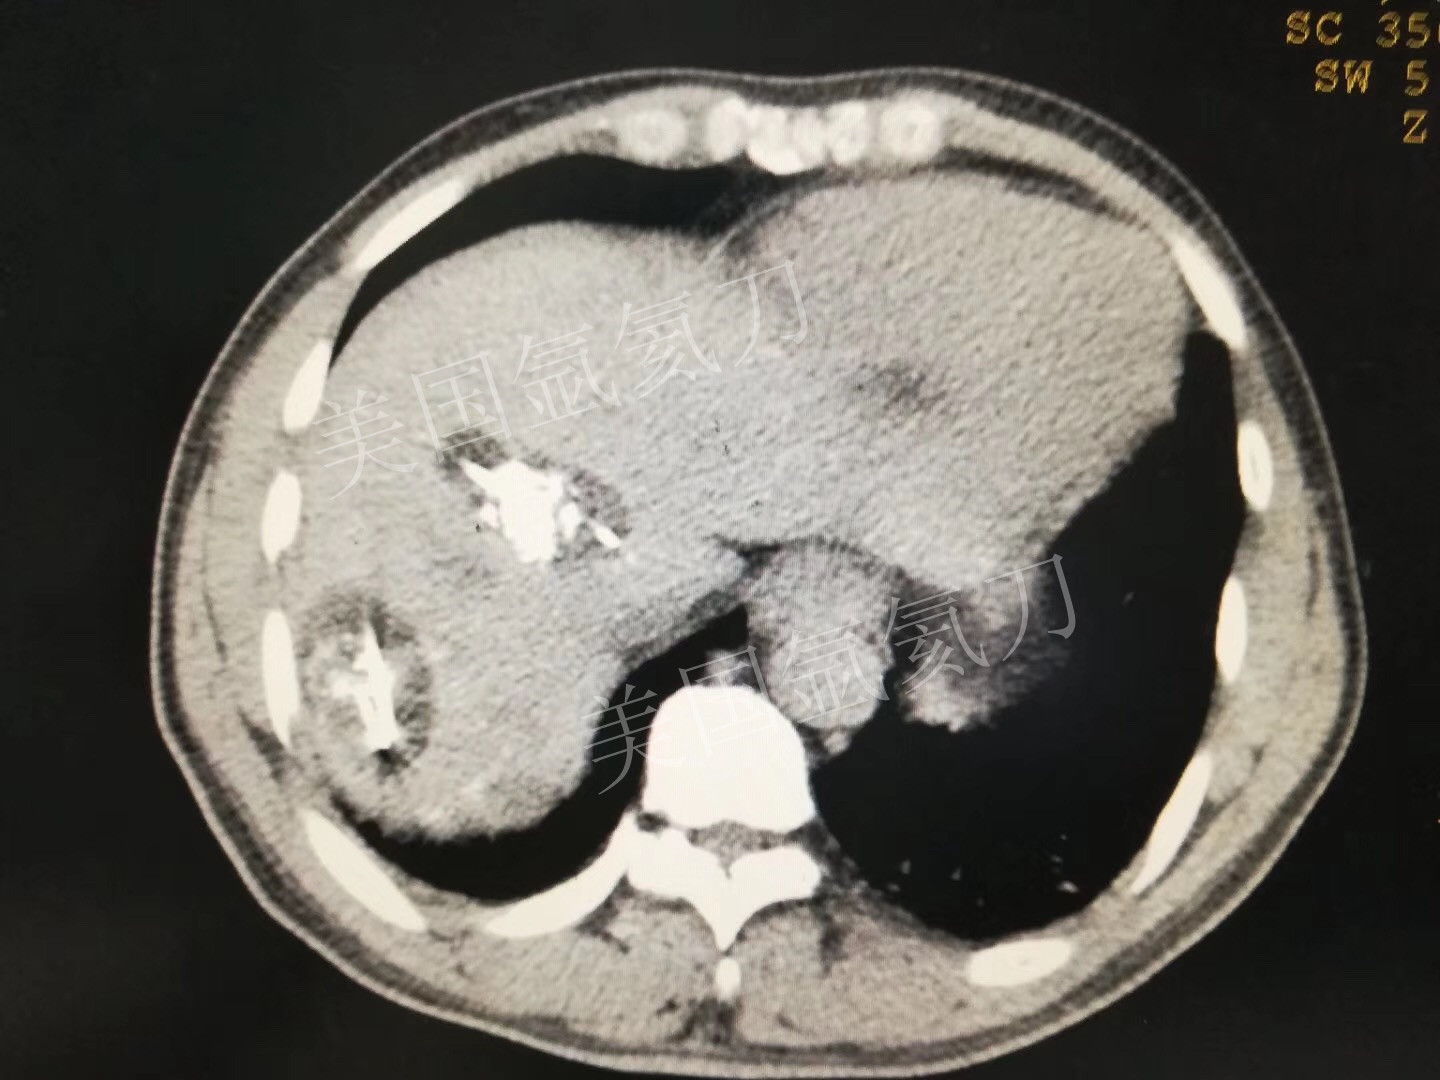

氩氦刀消融两个3公分介入后病灶,疗效确切!